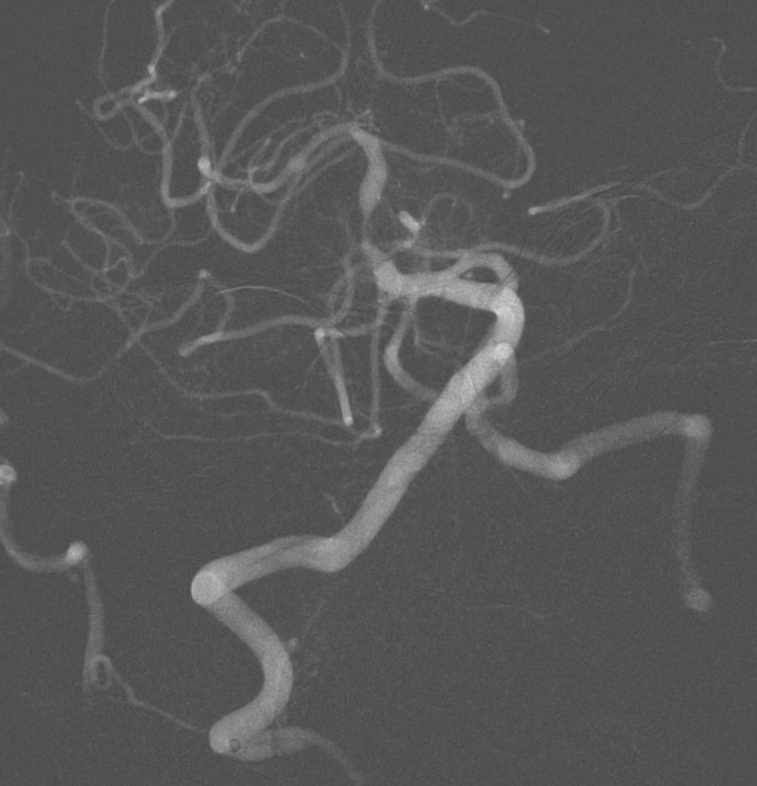

图3:术前造影显示:基底动脉中段重度狭窄,狭窄率95%。